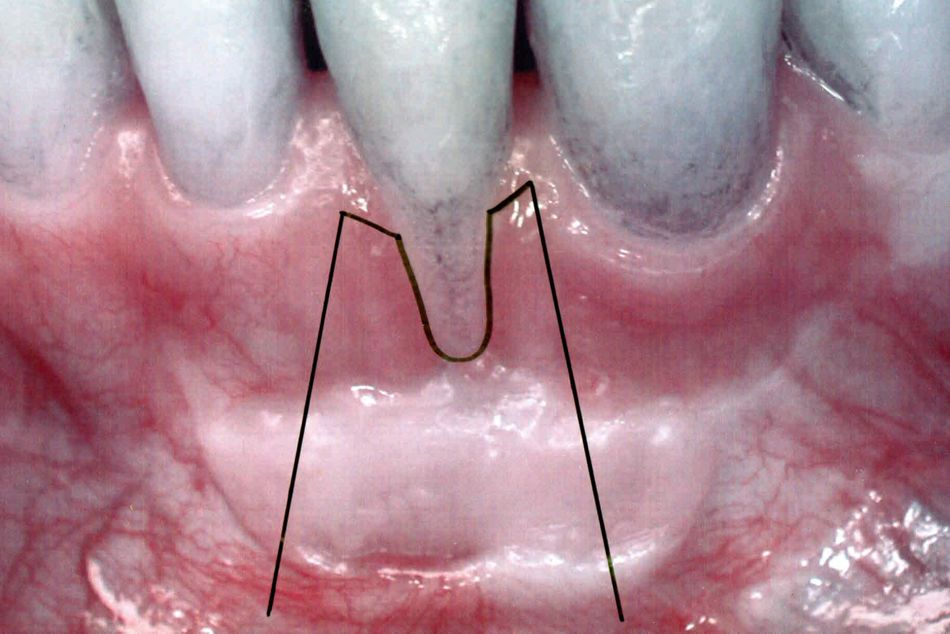

Die Patientin war vor 10 Jahren im Ausland in kieferorthopädischer Behandlung und hatte zum Abschluß einen verseilten Drahtretainer in der Unterkieferfront erhalten (Abb. 3). Seitdem wurden keine kieferorthopädischen Kontrollen mehr durchgeführt. Die Patientin wurde an unsere Praxis überwiesen mit der Anfrage, ob man bei der Rezession am Zahn 32 (Abb. 1 und 2) etwas ästhetisch verbessern könne.

Nach etwa 5 Jahren Vorbehandlung wurde eine chirurgische Rezessionsdeckung mit Emdogain in Lokalanästhesie durchgeführt. Zunächst wurde die freiliegende Wurzeloberfläche mit einer Bimssteinschlemmung gründlich gereinigt und die Oberfläche aufgerauht. Die horizontale Inzision erfolgte girlandenförmig direkt am Ansatz der Rezession in der Art und Weise, dass die beiden neuen Papillen schon vorgeschnitten wurden (Abb 10). Anschließend zwei vertikale Incisionen nach apikal divergierend, sodass sich ein Trapez ergibt. Ein full-thickness-flap (Mukoperiostlappen) wurde sorgfältig abpräpariert, was im Bereich des Schleimhauttransplantates aufgrund der Derbheit des Gewebes nicht ganz leicht war. Nach Darstellung der Wurzel, die sich wieder großteils im Knochen befand (Abb. 11), wurde diese nochmals mittels Handküretten sorgfältig gereinigt. Prefgel wurde aufgetragen und gemäß Herstellerangaben nach 2 Minuten mit Kochsalz abgespült. Emdogain wurde appliziert (Abb. 12) und der Schleimhautlappen nach Periostschlitzung und Deepithelisierung der beiden benachbarten Papillen im Sinne eines coronalen Verschiebelappens spannungsfrei vernäht (Abb. 13). Solcoserylsalbe wurde aufgetragen und die Patientin dahingehend instruiert, dass sie die mechanische Mundhygiene im Operationsgebiet für die kommenden 4 Wochen unterlassen und stattdessen mit einem Chlorhexidin spülen solle. Perioperativ wurde der Patientin ein Antibiotikum gemäß den allgemeinen chirurgischen Standards rezeptiert. Die Nahtentfernung erfolgte 11 Tage nach der Operation. Nach 4 Wochen wurde die Mundhygiene wieder auf eine mechanische Technik im Sinne einer rot-weiß-Bewegung mit einer feinen Handzahnbürste umgestellt.